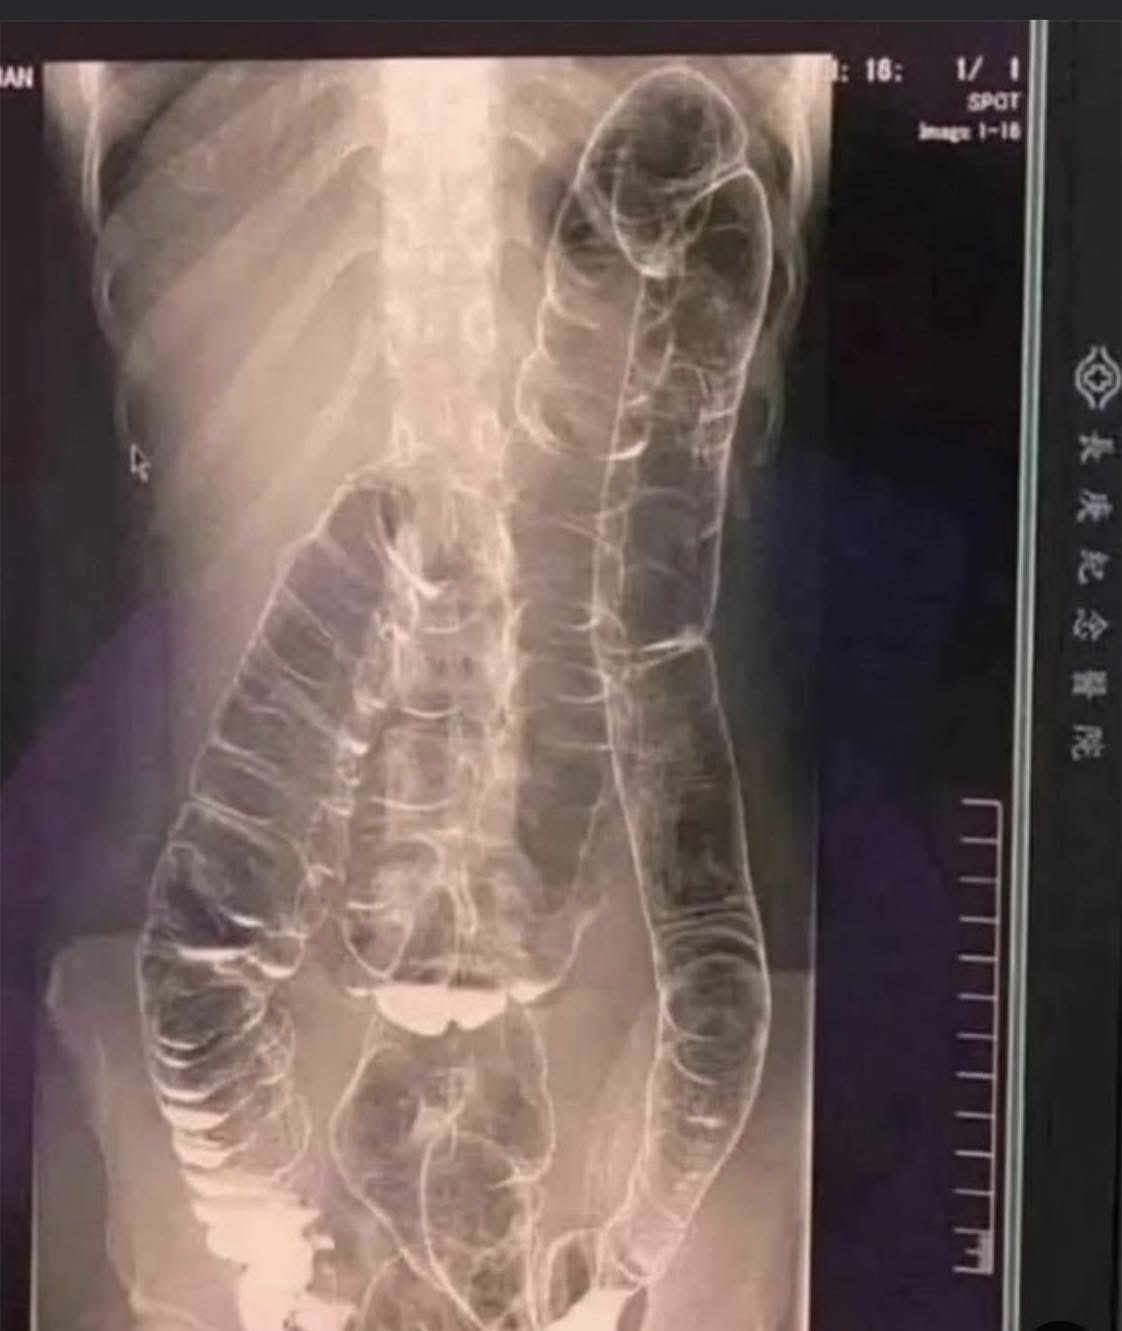

When waste accumulates in the colon due to an inefficient digestive system, it causes severe discomfort and bloating. Over time, the colon expands beyond its normal size, struggling to contain the excessive buildup of feces. In this case, medical imaging revealed a severely distended colon that had enlarged so much it reached up toward the chest, dangerously close to the heart. The stretching had nearly erased the colon’s natural folds and wrinkles, essential for its proper function. Left untreated, this condition could have led to life-threatening complications.